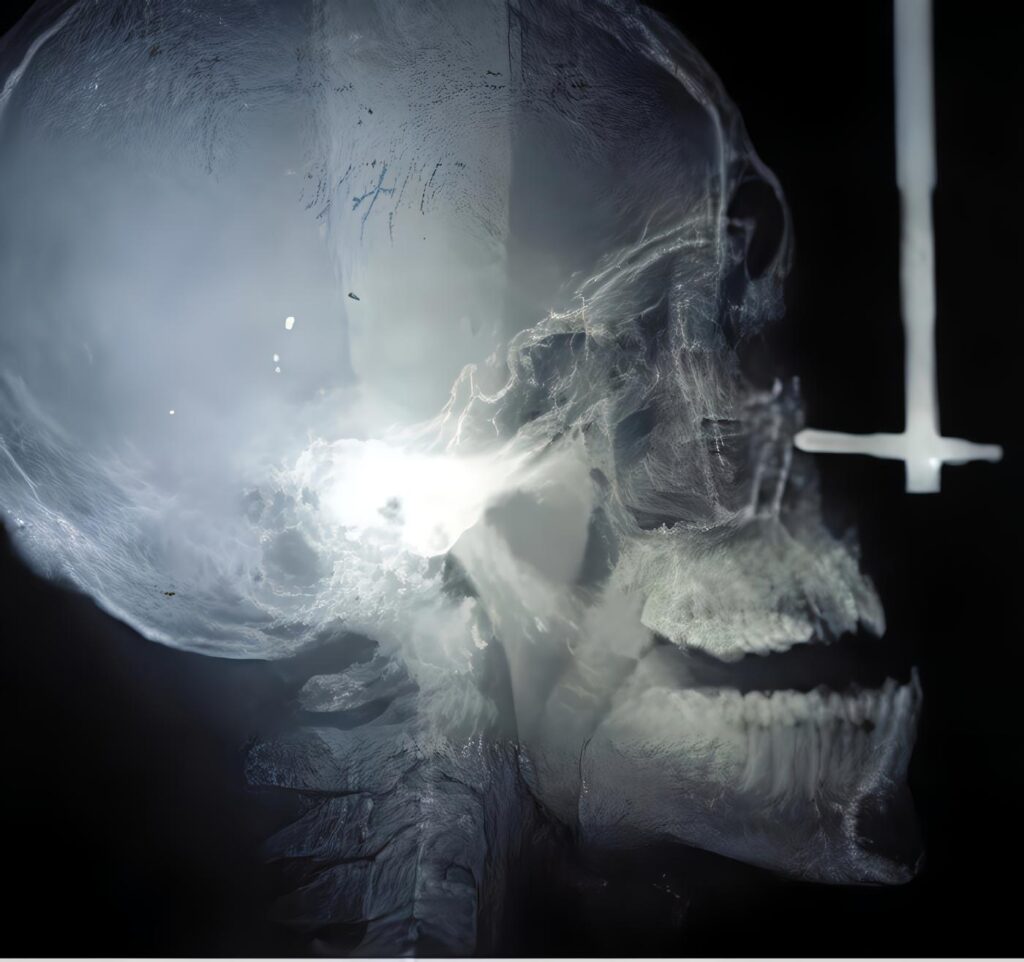

Manejo Odontológico Integral del Paciente con Labio y Paladar Fisurado

Dr. Germán Ramírez Yáñez Odontólogo Pediatra, Universidad Javeriana Universidad Tecnológica de México. El paciente con labio y paladar fisurado requiere...